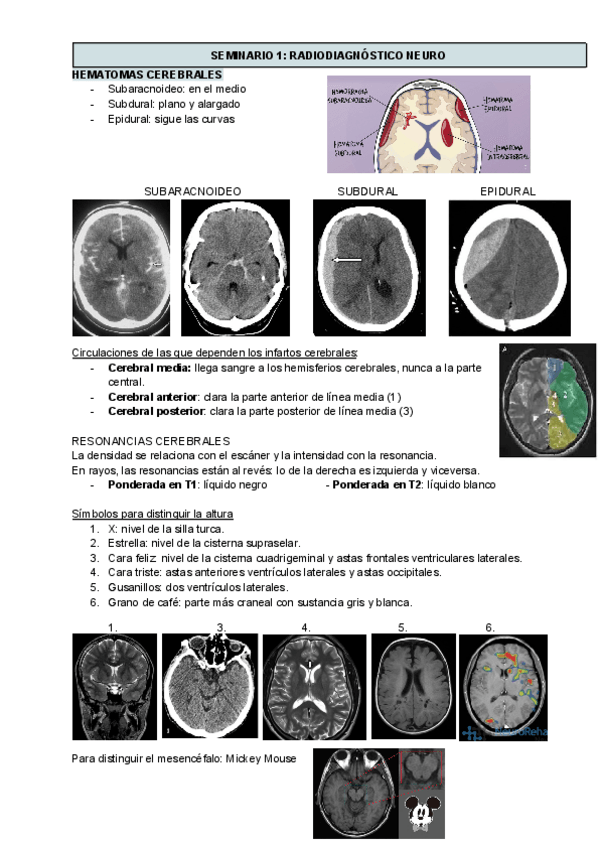

SEMINARIO-1-RAYOS.pdf